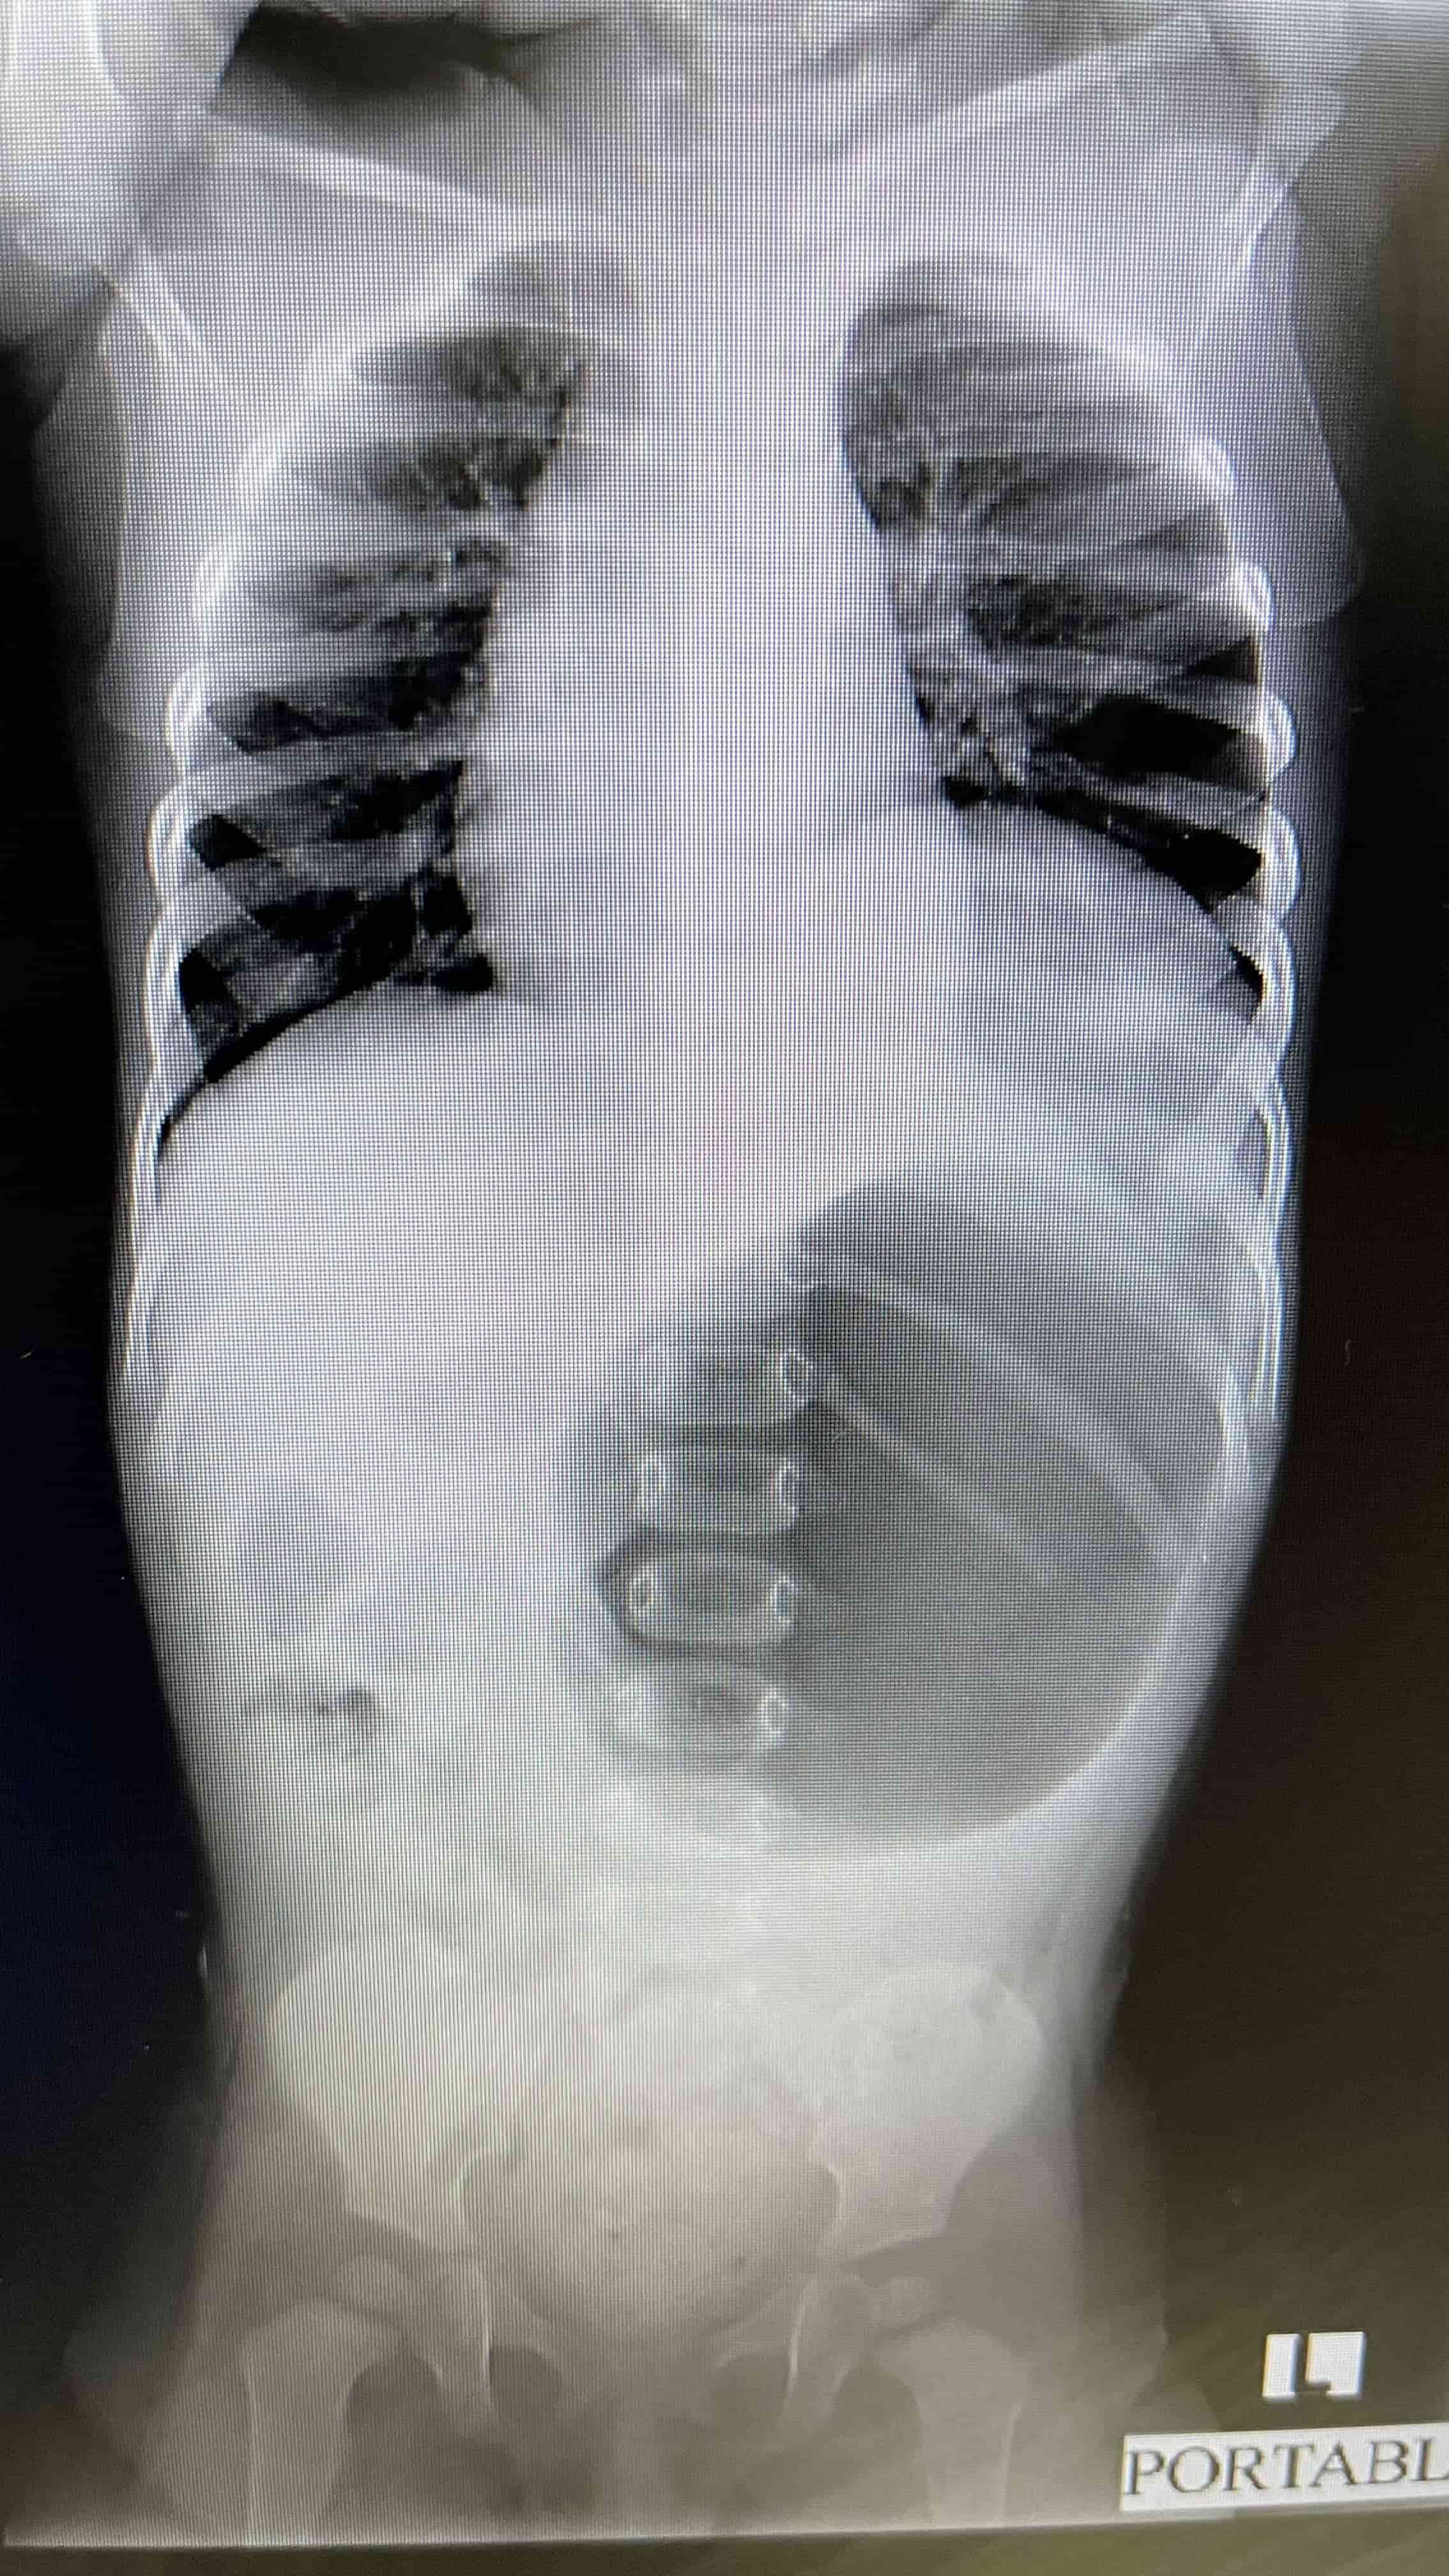

Médicos salvan la vida de infante con hernia diafragmática y estómago desplazado hacia los pulmones Radiografía de pecho y abdomen, luego de tratamiento con tubonasogástrico. Se demuestra mejoría marcada en desplazamiento deestructuras mediastinales. Médicos salvan la vida de infante con hernia diafragmática y estómago desplazado hacia los pulmones Placa lateral portable, se demuestra la hernia diafragmática Médicos salvan la vida de infante con hernia diafragmática y estómago desplazado hacia los pulmones Placa de pecho portable luego de reparación quirúrgica del diafragma.

Médicos salvan la vida de infante con hernia diafragmática y estómago desplazado hacia los pulmones Placa de pecho portable luego de reparación quirúrgica del diafragma.

"Se drenó bastante líquido y aire, e inmediatamente la niña abrió los ojos y comenzó a funcionar normal. La niña se recuperó rápidamente luego de una cirugía practicada. Si no hubiéramos actuado rápido, este panorama alentador no lo hubiéramos tenido. Como el estómago estaba empujando las zonas del mediastino, esto hace que la cantidad de sangre que llega al corazón sea mínima, lo que repercute en la circulación de la misma en tejidos periféricos y su actividad no es la misma que una persona normal, por ende puede haber presencia de sueño", detalló por su parte el Dr. Falcón.